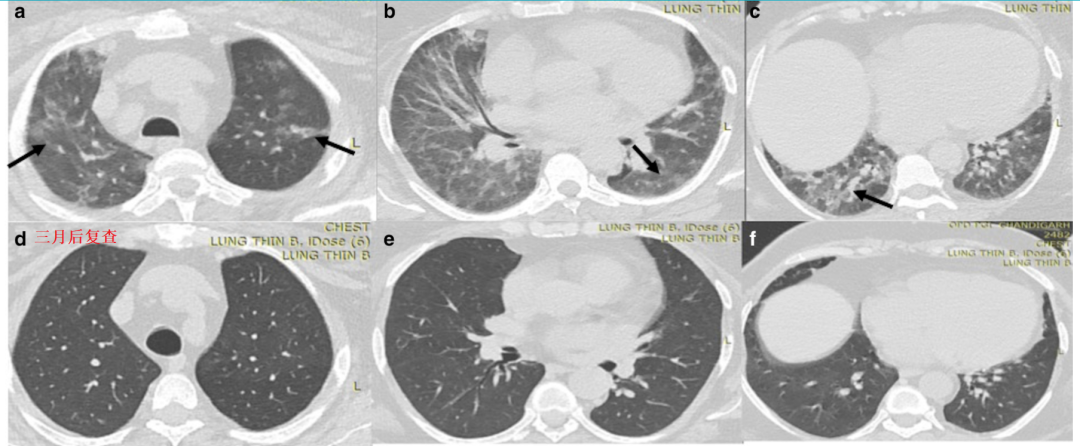

例1,一名69岁男性,新冠肺炎,继发血管侵袭性曲霉病,左下肺肿块,肿块内见小空洞,肿块周围见晕征(黑色实心箭头)。

例3,糖尿病患者,64岁男性,最近4天出现发烧、咳嗽和呼吸困难,诊断新冠肺炎。CT:右肺实变,空洞,右下肺静脉血管壁不规则和管腔狭窄,提示血管侵犯(图b箭头)。最终诊断:肺部毛霉菌病。

例4,HIV患者,感染新冠肺炎,图b显示病灶以中央分布为主,胸膜下相对少,最终诊断合并肺孢子菌肺炎。